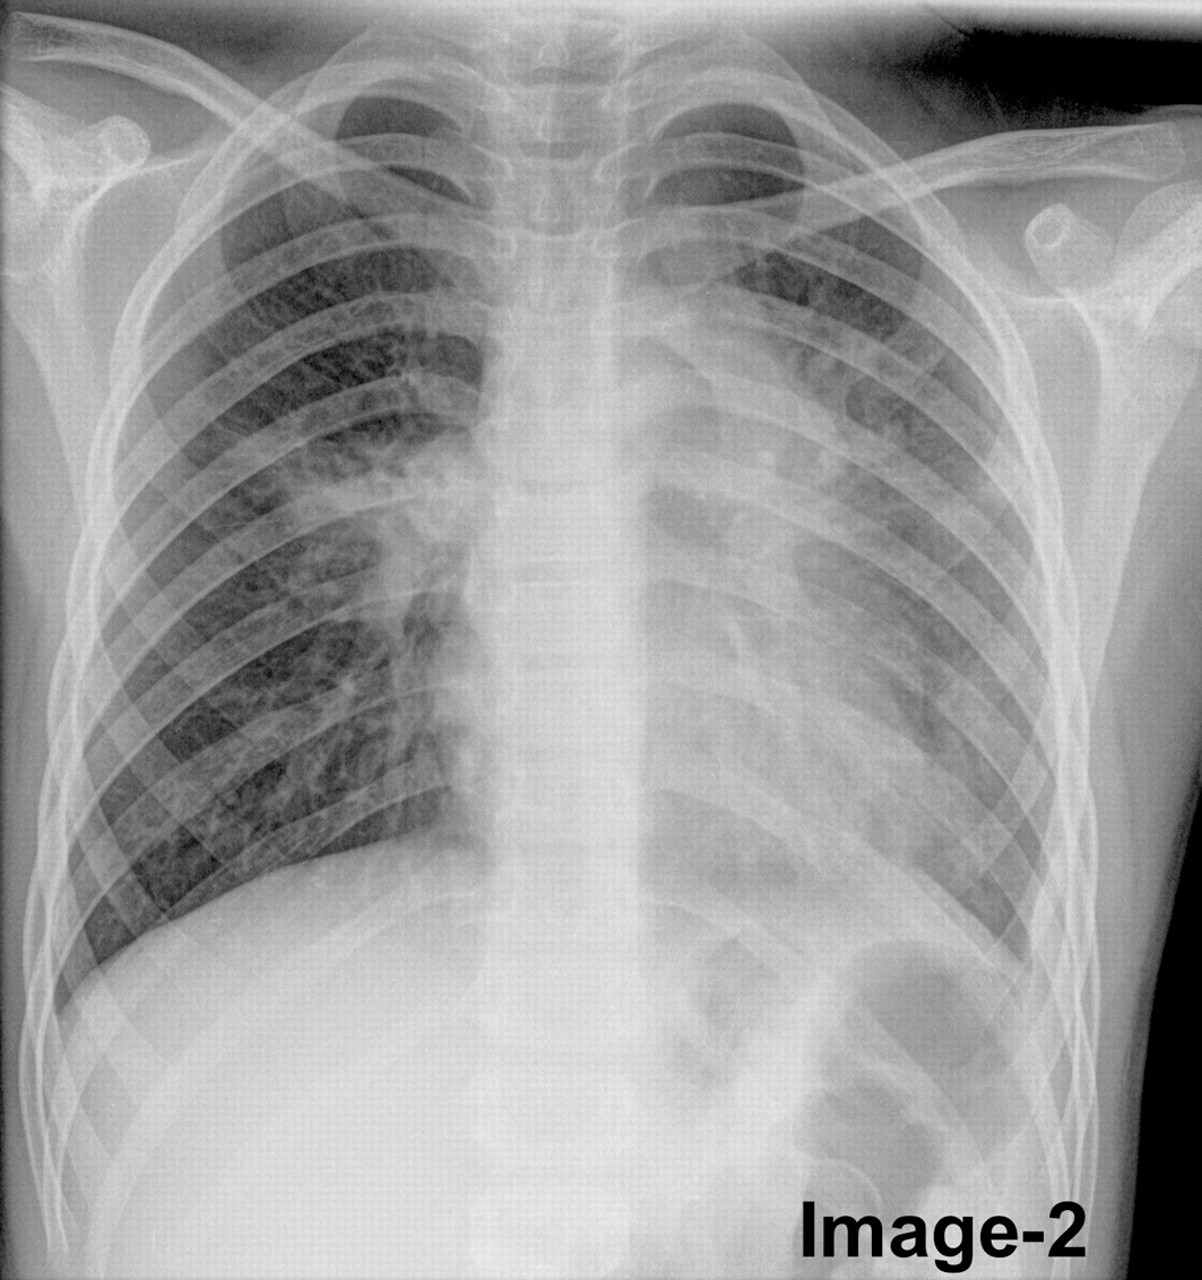

Zapalenie płuc na zdjęciu rentgenowskim ujawnia się przede wszystkim jako typowy obraz RTG przy zapaleniu płuc, z widocznymi zmianami w tkance płucnej. Obraz radiologiczny zależy od stadium choroby i patogenu, ale podstawowe są obszary zacienienia. Wczesne stadium może pokazywać jedynie nieostre zamglenie, w czasie gdy zaawansowane zapalenie objawia homogenne zagęszczenie.

Charakterystyczne infiltraty i konsolidacje w RTG płuc

Konsolidacja płucna, czyli konsolidacja płucna, stanowi podstawowy objaw i pojawia się jako jednorodne zacienienie zajmujące segment lub płat płuca. Na zdjęciu RTG widać wyraźne granice zmian, często z powietrznym bronchogramem – czarnymi oskrzelami na tle białego tła. W zapaleniu bakteryjnym, np. pneumokokowyminfiltraty są lobarne i zajmują dolne płaty w 70-80% przypadków. Zapalenie płuc na zdjęciu rentgenowskim może imitować atelektazę, ale obecność gorączki i leukocytozy pomaga w różnicowaniu.

Bakteryjne zmiany są najczęściej jednostronne i ostre, z wyraźnym air bronchogramem – widocznymi oskrzelami wypełnionymi powietrzem na tle zacienionego miąższu. Wirusowe zapalenie płuc, np. wywołane grypą lub RSV, prezentuje się inaczej: dominują międzypłatowe nacieki o charakterze międzywrzodowym, rozproszone obustronnie. Te ziarniste lub siateczkowate zmiany zajmują oba płuca w 60-90% przypadków, bez homogennej konsolidacji.

Wirusowe postacie zapalenia płuc na zdjęciach rentgenowskich klatki piersiowej często przypominają obrzęk płucny, z perihilarnymi smugami i zagęszczeniami w dolnych polach. Bakteryjne zapalenie płuc wykazuje z kolei szybką ewolucję – konsolidacja może ustąpić po 48-72 godzinach antybiotykoterapii, co potwierdza RTG kontrolne. Frazy takie jak charakterystyczne cechy bakteryjnego zapalenia płuc w rentgenie pomagają radiologom w szybkim różnicowaniu.